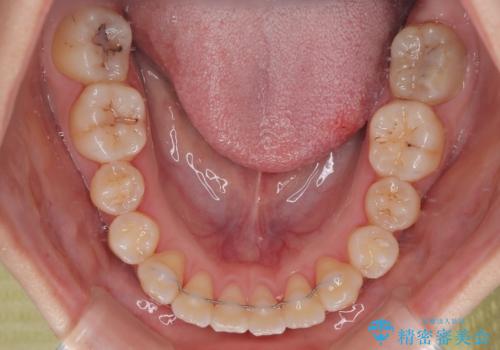

診査の結果、上下顎ともに叢生が認められましたが、ワイヤー矯正・マウスピース矯正のいずれでも対応可能な症例でした。

という患者様のご希望を踏まえ、プラスチックブラケット+コーティングワイヤーを用いたワイヤー矯正を選択しました。

金属色が目立ちにくく審美性が高い

確実に歯を動かせるため治療計画が立てやすい